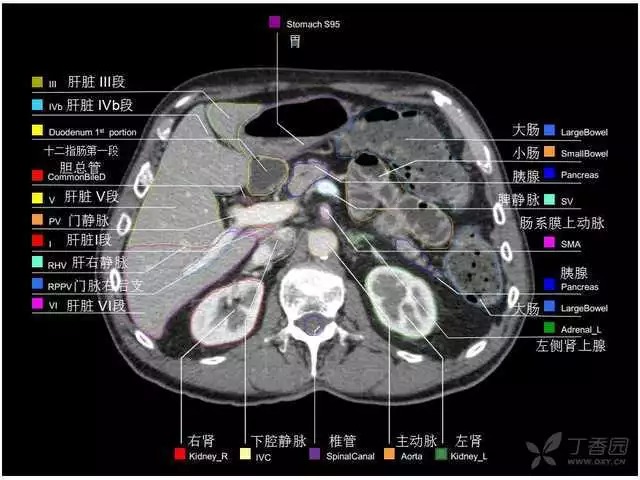

腹部肝脏高清CT断层的图谱

全腹部高清CT图谱,淋巴结彩色图谱,血管解剖图谱大汇总!

肝段,肝内管道的分布规律

美国放射学会ACR官网,对肝脏的区域和节段解剖学概述